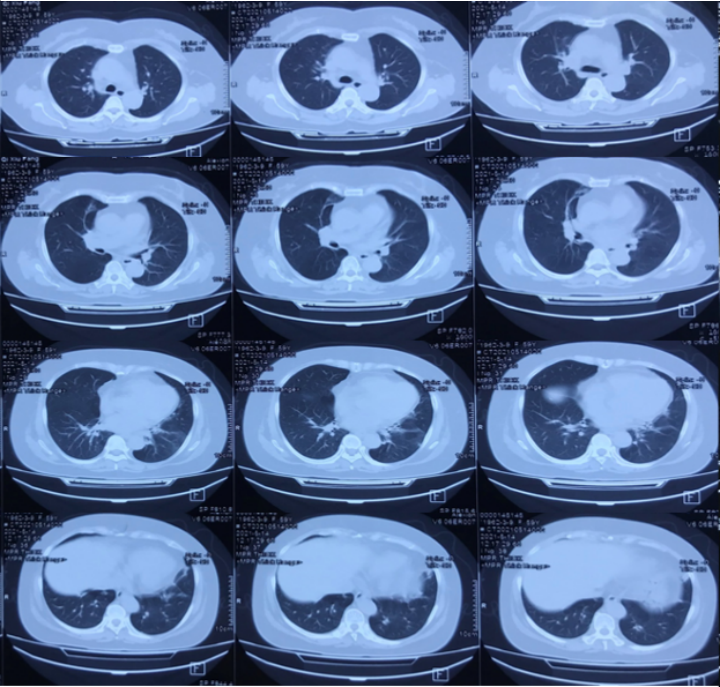

手术当天及术后2天床旁胸片如图4所示。术后第2天更换气管导管,右肺出现实变影。

图片

图4  患者手术当天及术后胸片

经过多次气管镜清理,患者氧合指数稳步升高(表2)。6月1日(D13)撤机,予经鼻高流量氧疗。6月2日(D14)复查胸片提示左肺吸收较明显(图7)

图7  复查胸片

6月12日复查胸部CT提示左肺吸收良好,左肺舌段复张。6月14日患者好转出院。